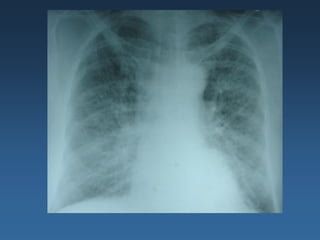

Radiografia Tórax: Aumento de área cardíaca, padrão de inversão

de trama vascular, discreto derrame pleural a direita.